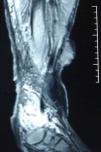

Se trata de un varón de 72 años, sin antecedentes personales de interés salvo un síndrome postrombótico desde hacía 30 años tras un traumatismo, con una úlcera venosa de 8 años de evolución; el paciente fue remitido a nuestra consulta por empeoramiento de ésta en los últimos meses. A la exploración presentaba una úlcera extensa en la cara anterointerna infragenicular de la extremidad inferior izquierda, con una excrecencia sobre su superficie de unos 10cm de diámetro (fig. 1). Con la sospecha de degeneración neoplásica de la úlcera, se le realizó un estudio radiográfico en el que se descartó la afectación ósea, así como un estudio con resonancia nuclear magnética en el que se observó que la masa estaba confinada en los planos superficiales, sin traspasar la fascia muscular, y también se descartó la presencia de adenopatías metastásicas locorregionales (fig. 2). Se decidió entonces realizar la exéresis de la neoformación, intentando dejar márgenes amplios libres de enfermedad así como la fascia muscular por debajo de la masa. Se remitió la pieza para un estudio anatomopatológico, en el que se observó la presencia de células fusiformes con alto índice mitótico, positivas para actina, vimentina y CD68, y se diagnosticó de HFM subtipo pleomórfico. Además, la presencia del marcador Ki-67 positivo en más del 20% de las células indicaba una gran agresividad de éste. Se envió entonces al paciente al Servicio de Oncología, donde no se realizó ningún tratamiento adyuvante. A los 3 meses presentó recidiva de la neoformación, con hemorragias de repetición y anemización importante, así como importante afectación tisular que hacían inviable la extremidad, por lo que se decidió realizar amputación supracondílea de ésta.